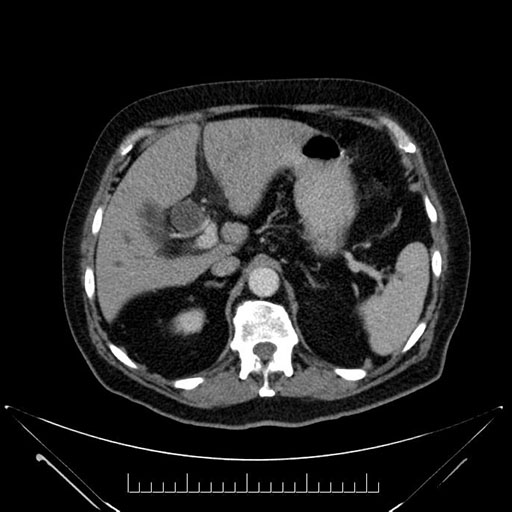

Axial - 3 months prior

Axial - stented